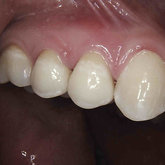

He received his Diploma in Implantology in 2016 from the University of Pretoria, which he passed with Distinction. He is also a member of the International Team for Implantology (ITI), which is based in Switzerland and offers members access to the latest research and cutting-edge techniques.

Porcelain crowns and restorations made in one appointment.

We make it a priority to incorporate the latest in dental technology in everything we do at our practice. ...